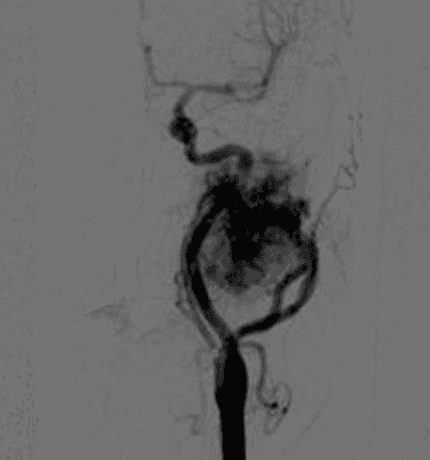

Al ser un tumor muy vascularizado, es conveniente unos días previos a la resección quirúrgica, hacer una arteriografía selectiva de la bifurcación carotidea, localizar la o las arterias nutrientes del mismo y embolizarlas (ocluirlas). De esta maneras disminuimos la vascularización del tumor y la resección quirúrgica se facilita.